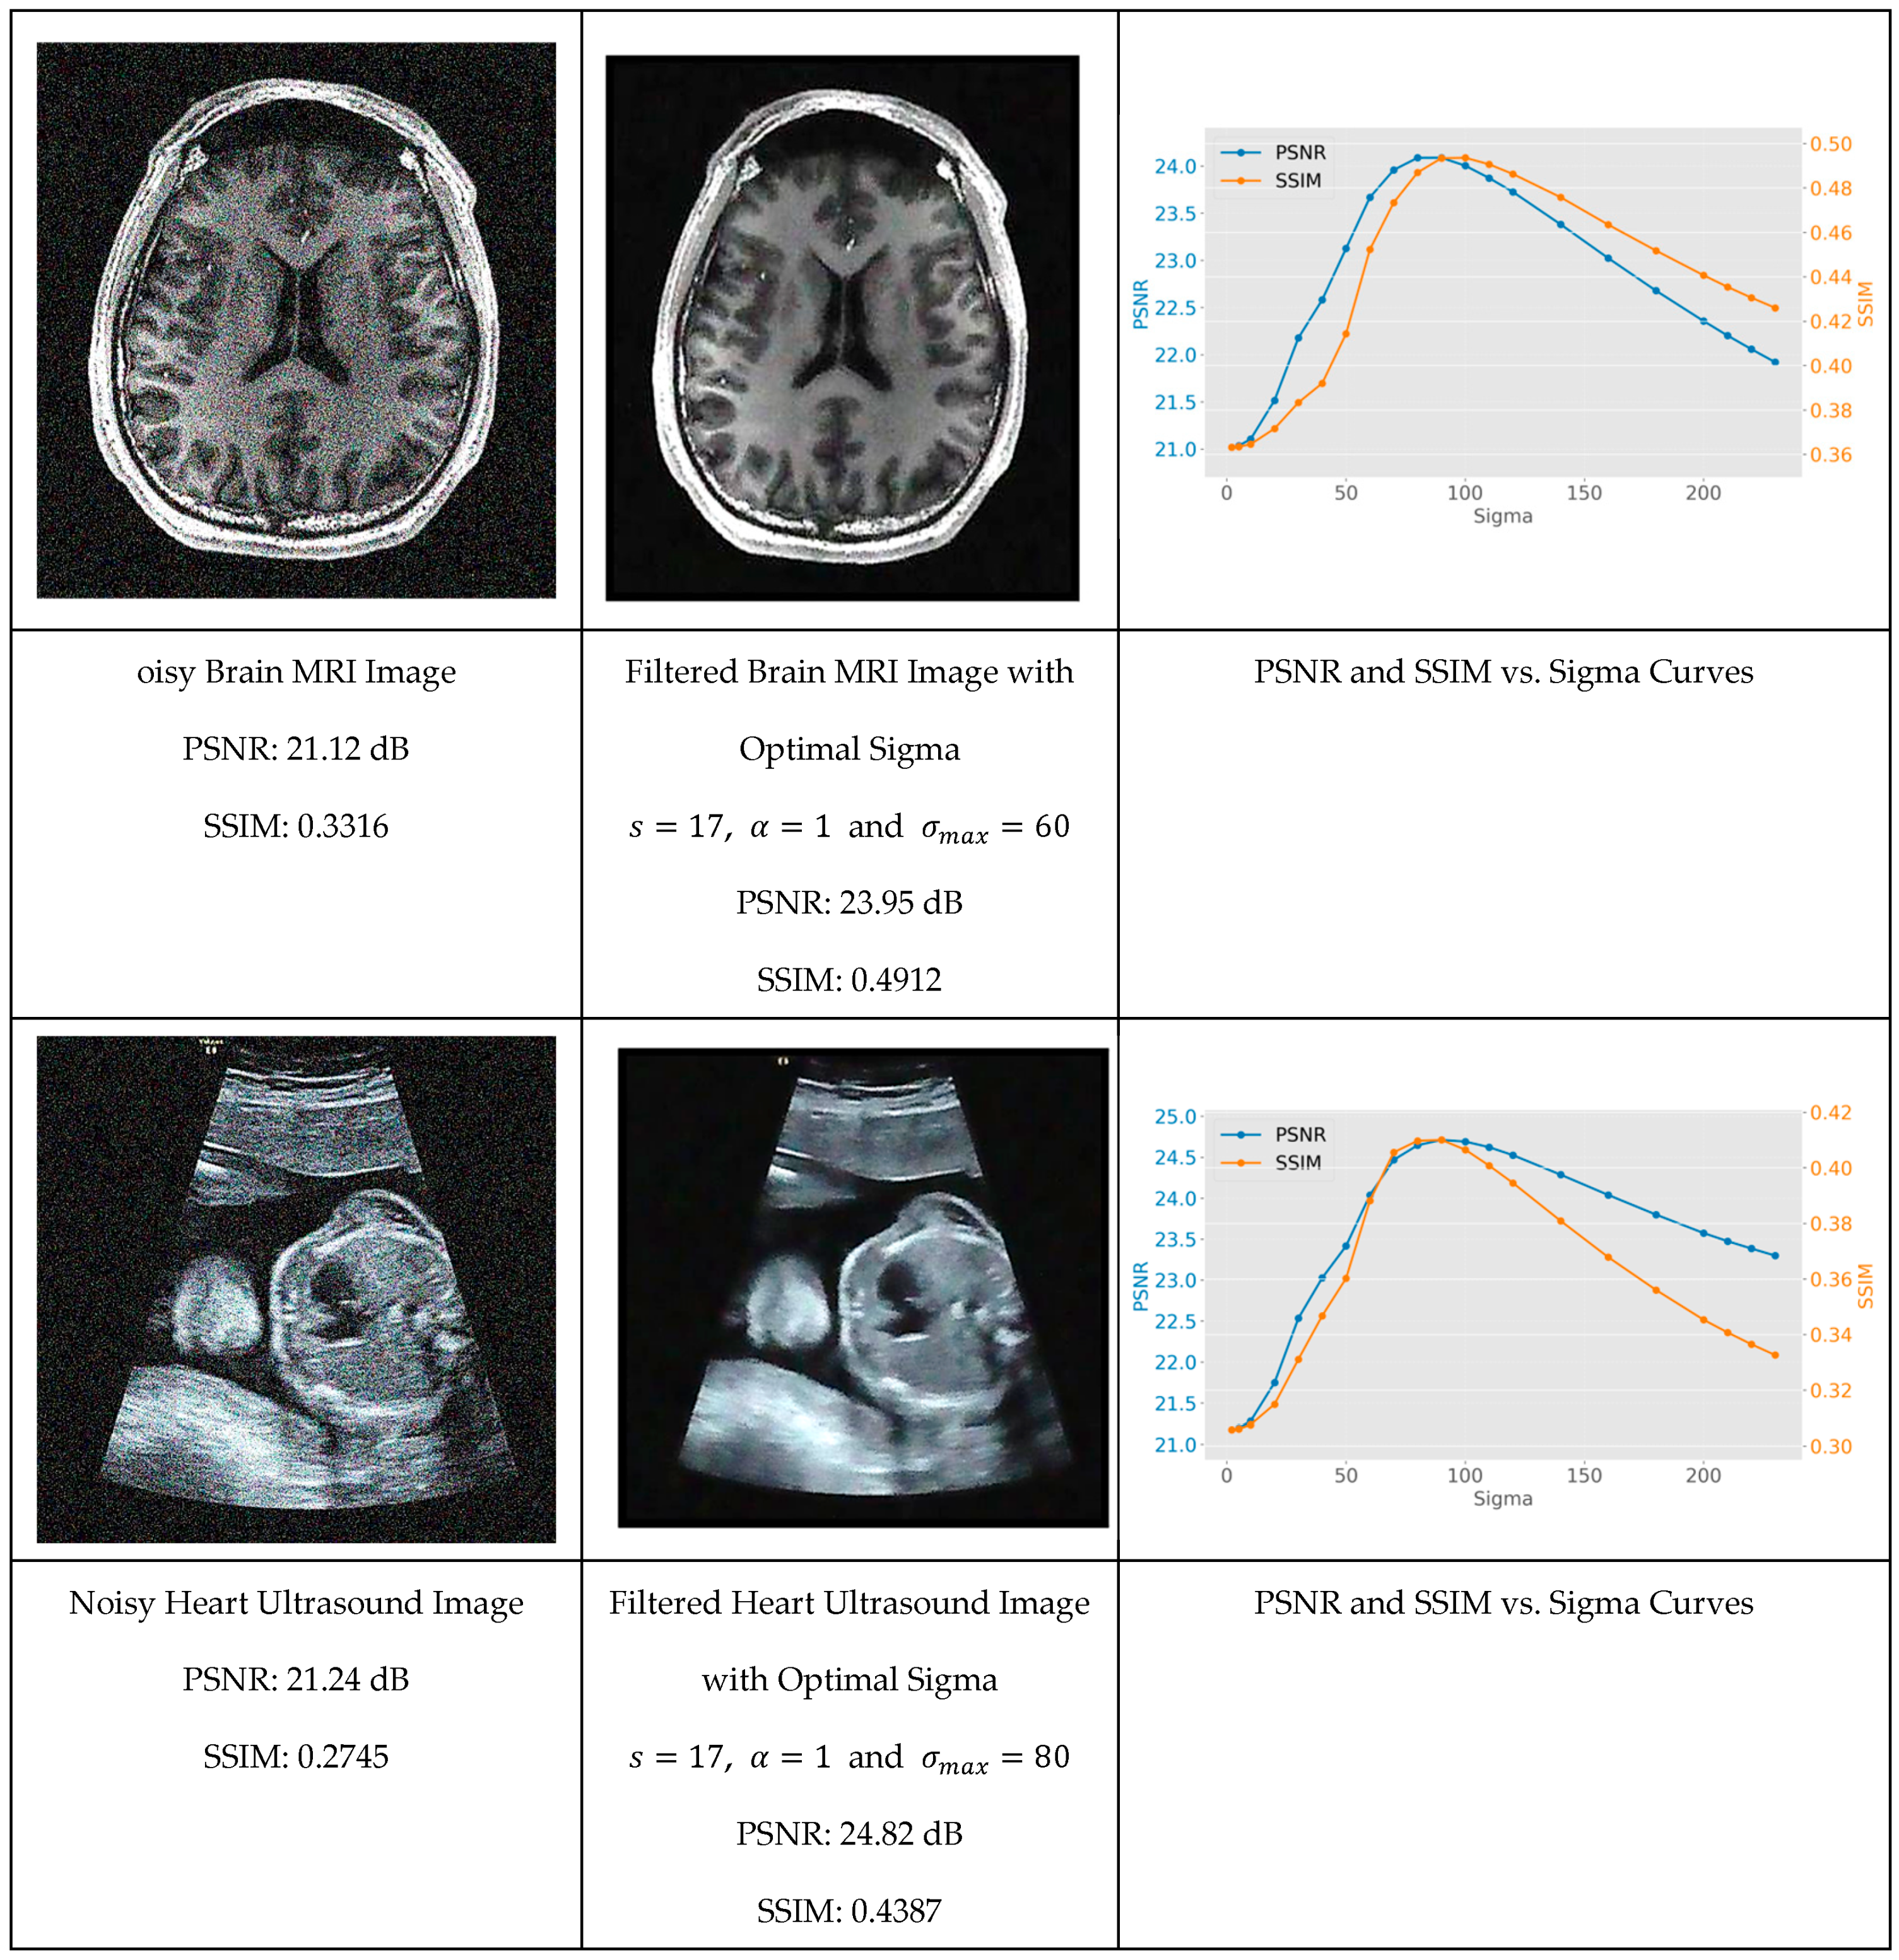

Figure 8 shows the original image with Gaussian noise, the filtered version for corresponding to the maximum of the PSNR, and finally the evolution of the PSNR and SSIM as a function of . One can see, for each image, the PSNR and SSIM evolve as a function of monotonically toward a maximum and then reduce due to over blurring. The value corresponds to the maximum PSNR and is called the natural scale of the image.

Figure 8.

Evolution of the PSNR and SSIM as a function of for a noisy version of the dataset images. Left: The noisy image. Center: The image filtered with the optimum value . Right: The evolution of the PSNR and SSIM vs. .

The experimental results reveal that while the natural scale parameter varied across different images (with test cases showing a range from = 60 to = 90), it can be systematically identified through careful analysis of PSNR and SSIM metrics. This discovery provides researchers with a methodical framework for parameter optimization that eliminates the traditional trial-and-error approach commonly required in advanced filtering techniques.